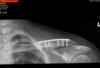

Interpretation of laboratory and imaging studies with notes most notable for left midshaft clavicle fracture with greater than 100% displacement and 2 cm shortening.

Once in the operating room the patient was placed in the beachchair position with intraoperative fluoroscopy used to confirm fracture site as well as assist in plate and screw placement as well as reduction confirmation. Anesthesia placed an interscalene block with local lidocaine and Marcaine placed by me.

My surgical approach was directly over the clavicle including skin soft tissue skin flaps intact dissecting down through the platysma.. I was able to control fracture fragments and when I evaluated the fracture I identified comminution at the fracture so I did not place a lag screw. The fracture fragment did allow for compression using the plate. I used a superior plate location , 7 hole, titanium with some contouring. I placed on screw within the distal bone, followed by an eccentric screw on the other side of the fracture (away from the fracture)to compress the fracture. I then placed 3 3.5mm cortical screws bi cortically on each side which is excellent purchase into the bone for plate stabilization. I confirm fracture reduction and instrumentation fluoroscopically at the end of the case. Surgical time was approximately 1 hour with blood loss of 25cc estimated. Patient had very good bone and head I had excellent purchase using cortical screws x 6; I did not feel there was any need for additional locking screws for stabilization. I was concerned one screw was close to the fracture site I was able to get excellent purchase I did not feel I needed to fortify that with a locking screw. Wounds were closed in layers with monocryl subcutical closure